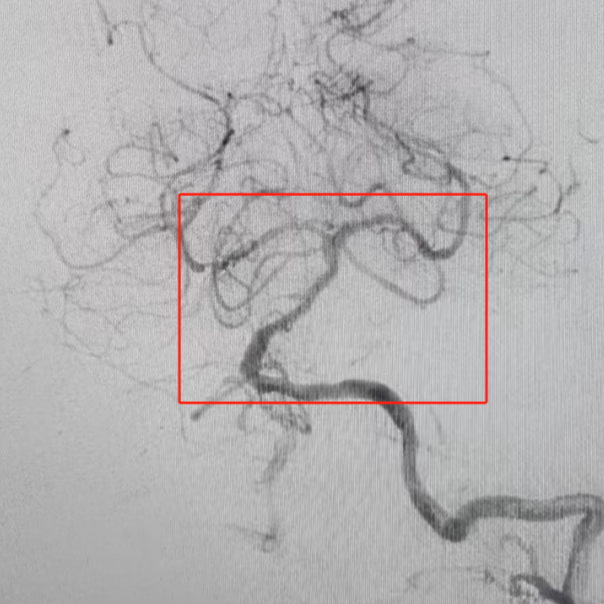

手術(shù)團(tuán)隊(duì)在影像引導(dǎo)下發(fā)現(xiàn)患者血管條件極差:雙側(cè)椎動(dòng)脈扭曲,優(yōu)勢(shì)椎動(dòng)脈開口處扭曲伴狹窄,基底動(dòng)脈重度狹窄。主刀醫(yī)師憑借豐富經(jīng)驗(yàn),建立導(dǎo)管通路。隨后,團(tuán)隊(duì)精準(zhǔn)實(shí)施顱內(nèi)動(dòng)脈取栓+基底動(dòng)脈球囊擴(kuò)張成型術(shù),僅用40分鐘便開通血管,恢復(fù)腦干及小腦血供。術(shù)中需克服血管迂曲、血栓逃逸等高風(fēng)險(xiǎn)因素,每一步操作均需毫米級(jí)精準(zhǔn)控制,稍有不慎即可引發(fā)血管破裂或血栓擴(kuò)散。

術(shù)前基底動(dòng)脈重度狹窄

術(shù)后基底動(dòng)脈狹窄解除